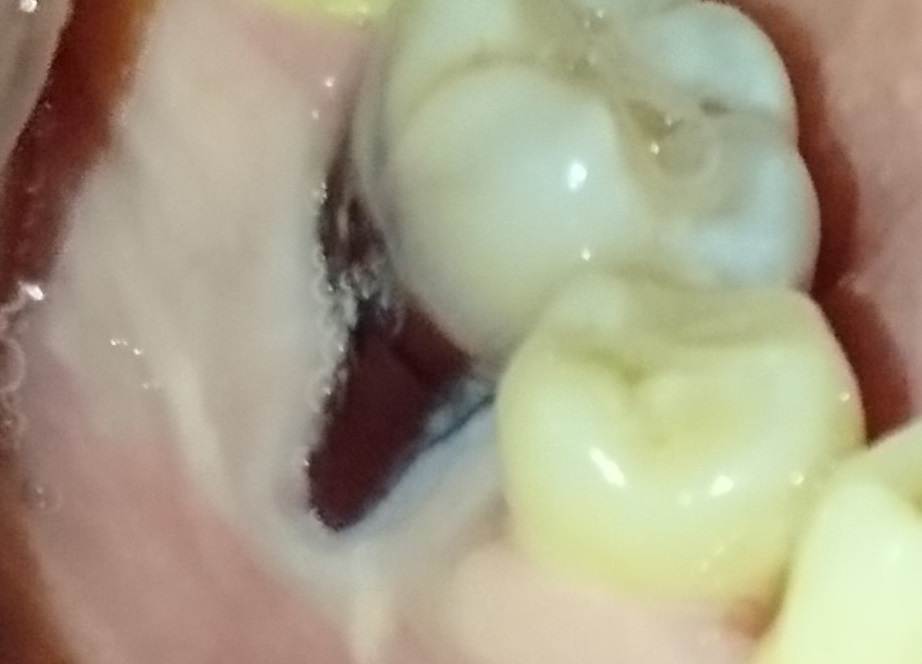

Chernichniy Опубликовано 25 апреля Поделиться Опубликовано 25 апреля Привет всем ! Подскажите, пожалуйста, на шестом мертвом зубе слева сильное опущение десны. Сам зуб был пролечен 31 год назад с удалением нерва. Старую пломбу поменял на современную в 2017году. Сделали КТ пару дней назад, она показала опущение костной ткани именно под этим зубом на 4 мм, сам зуб обозначил как "безнадежный" , в перспективе должна появиться подвижность и тогда его нужно будет удалить. Сам зуб отличается по цвету эмали, имеет более серый оттенок и может чуть фиолетовый. Возможно, такой цвет из-за состава старой пломбы. Спросил , нужно ли его удалять сейчас и ставить имплант или искусственную костную ткань ? Ответили, сейчас нет никакой подвижности и зуб крепкий, необходимости удалять его -нет, но вкладываться в лечение этого зуба мы бы не стали. 1)Можно ли как-то почистить десневой карман до белого цвета? Как называется такая процедура? Сам камень имеет неоднородную поверхность, бывает , что скалывается, острые края, все дела.... 2)Можно ли как-то поднять десну пересадкой лоскута с неба? 3)Имеют ли смысл вообще процедуры по пунктам 1 и 2 ? могут ли отсрочить ли срок выпадения зуба? 4)Сейчас зуб стоит, "теряется" ли костная ткань под ним или нет? 5)Как в большинстве таких случаев поступают, удаляют зуб сразу или ждут "до последнего" ? 6)Если оставить зуб, может ли костная ткань опуститься до такого уровня, что имплант будет невозможно поставить? 7)Можно ли использовать точечно размягчитель зубного камня, если появляется острый скол? Ссылка на комментарий

Chernichniy Опубликовано 26 апреля Автор Поделиться Опубликовано 26 апреля Знал бы, на телефон сфотографировал Через три недели мелкий кариес пойду лечить планово, может быть КТ достану. Там в общем пару врачей по ней ответили одинаково, пломба, зуб и корни - нормальные, но есть опущение костной ткани на 4 мм. На КТ сам видел небольшую темную область между корней и всё, у других зубов такого нет. Вокруг зуба темных областей нет, только между корней. Шатали прямо руками - подвижности нет. Расскажите по гигиене, как убрать камень под десной, как называется процедура??? Названия операция, порядок процедур ... Если решим оставить зуб в мае.... Этот карман, как парус , всю еду собирает. Ссылка на комментарий

Chernichniy Опубликовано 13 часов назад Автор Поделиться Опубликовано 13 часов назад Я снова тут! Нашел КТ , снимки примерно одинаковые, пломбированный шестой зуб. Между корней нет костной ткани. В июне пойду на прием ... Кто что думает? Ссылка на комментарий